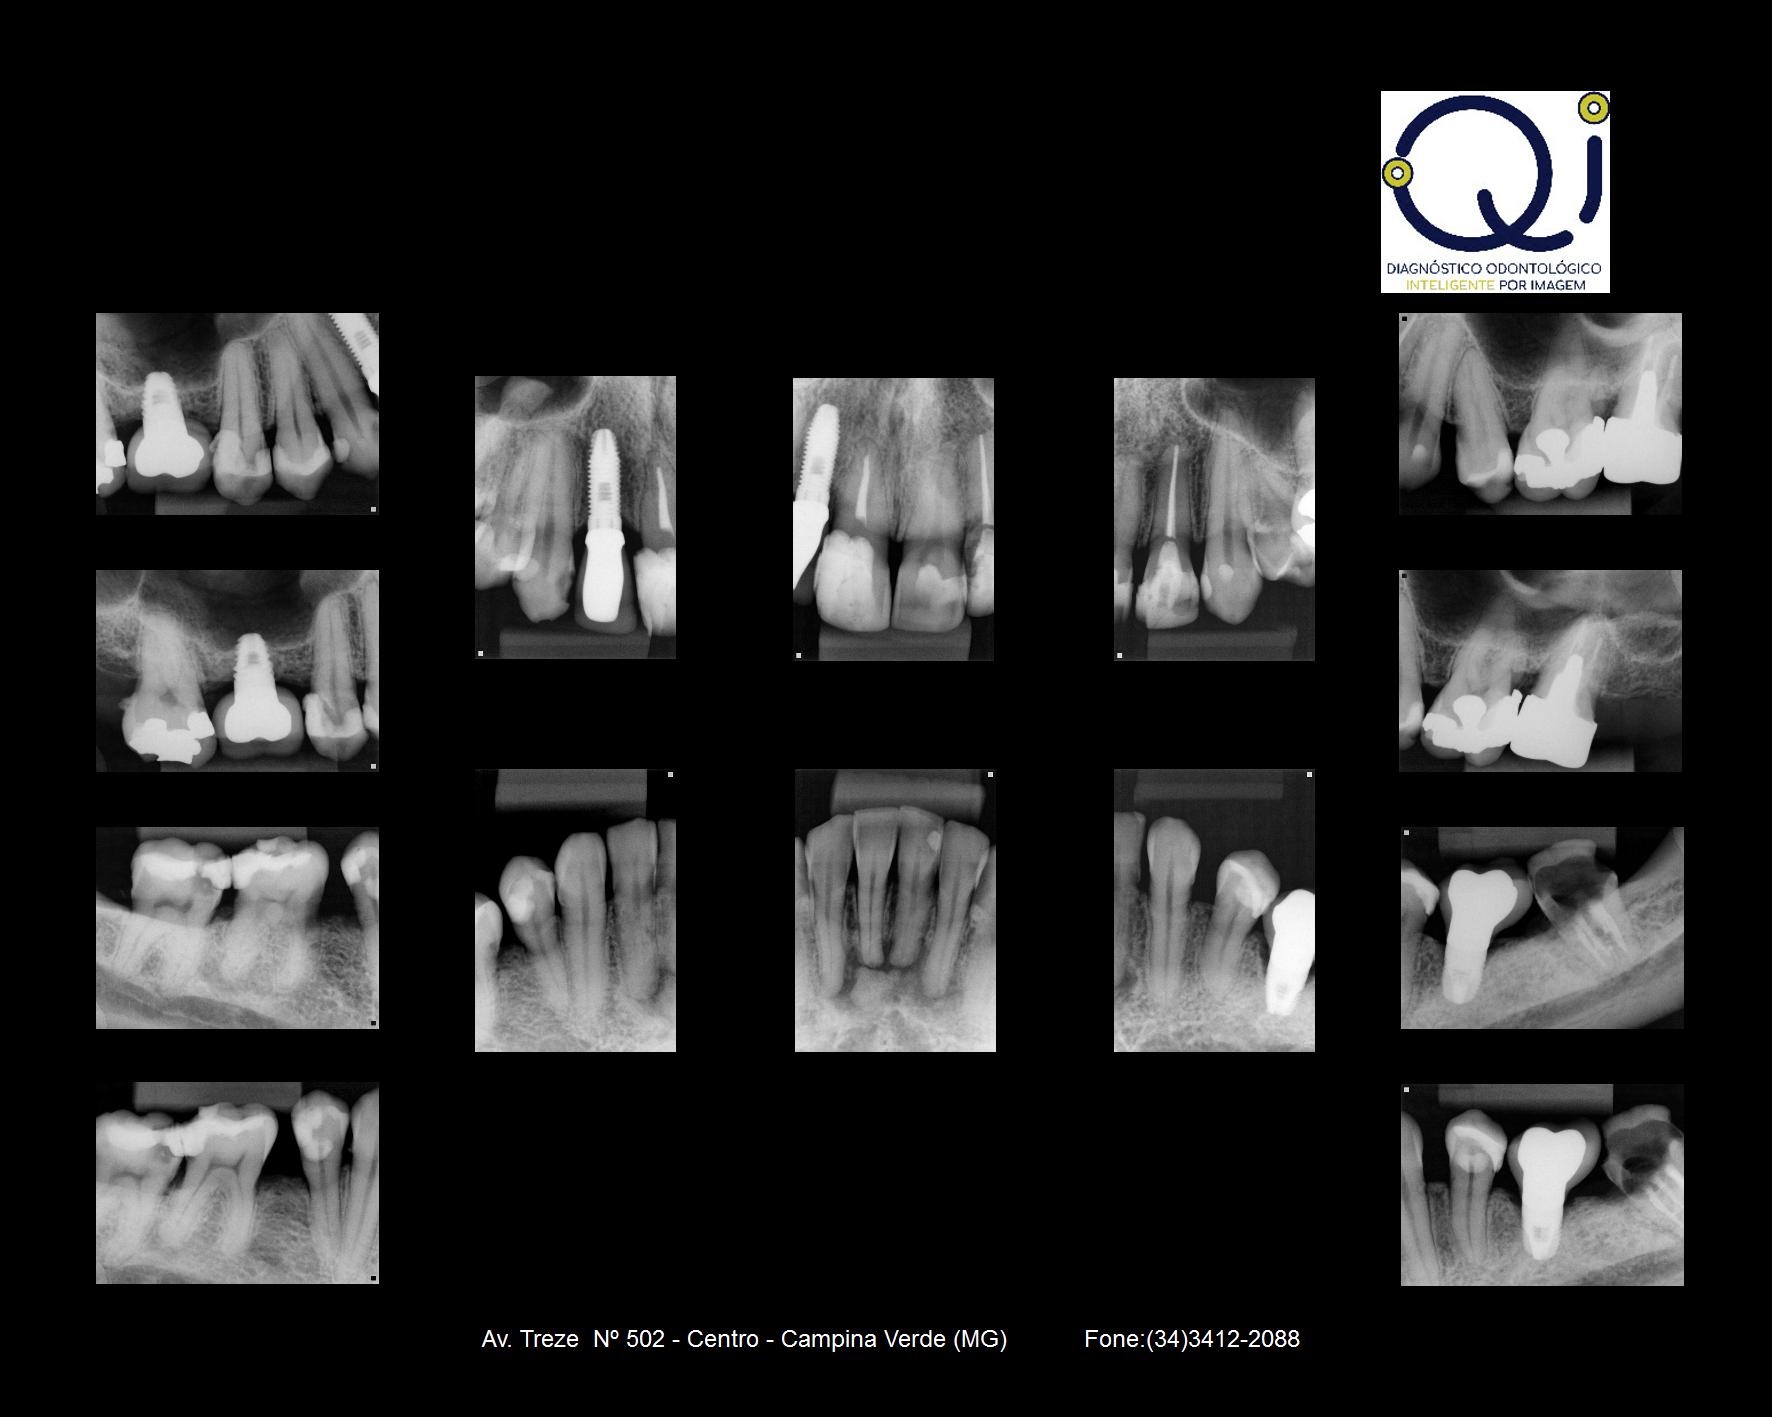

Radiografia Interproximal

Este exame radiográfico visualiza as faces proximais dos dentes posteriores observando-se simultaneamente as coroas dentárias dos dentes superiores e inferiores, e é indicado para a pesquisa de:

- cáries (proximais e incipientes).

- excesso ou falta de materiais restauradores.

- reabsorção da crista óssea alveolar (indicativa de doença periodontal).